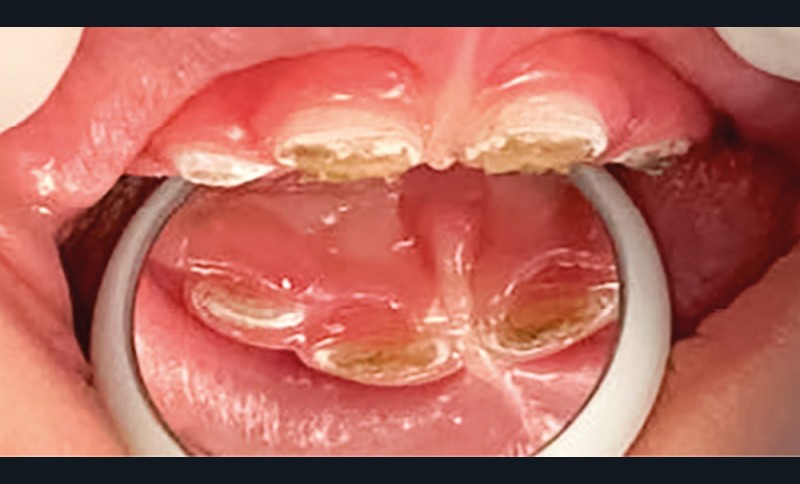

- L’évolution de la maladie carieuse : cette pathologie bactérienne, multifactorielle, se transmet très vite d’une dent à une autre dans la cavité orale de l’enfant. Ainsi, avant l’âge de 6 ans, la carie précoce de l’enfant (CPE) peut atteindre un stade sévère et ne plus permettre à l’enfant de mastiquer sans douleur (fig. 2).

- La perte de chance pour le développement : la CPE non traitée va entraîner l’avulsion précoce de certaines dents, induisant des troubles alimentaires pouvant se répercuter sur le développement général de l’enfant (croissance et développement cognitif), voire de sa vie sociale (absences scolaires répétées, pas de sourire). La CPE a un impact négatif sur la qualité de vie de l’enfant.